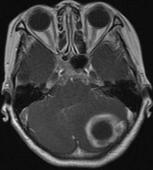

颅内动脉瘤

628健康网为您分享有关颅内动脉瘤的症状,颅内动脉瘤的治疗方法,颅内动脉瘤的预防知识,颅内动脉瘤的症状图片,颅内动脉瘤...

急性硬脑膜外血肿

628健康网为您分享有关急性硬脑膜外血肿的症状,急性硬脑膜外血肿的治疗方法,急性硬脑膜外血肿的预防知识,急性硬脑膜外血...

小儿颅内出血

628健康网为您分享有关小儿颅内出血的症状,小儿颅内出血的治疗方法,小儿颅内出血的预防知识,小儿颅内出血的症状图片,小...

小儿脑脓肿

628健康网为您分享有关小儿脑脓肿的症状,小儿脑脓肿的治疗方法,小儿脑脓肿的预防知识,小儿脑脓肿的症状图片,小儿脑脓肿...